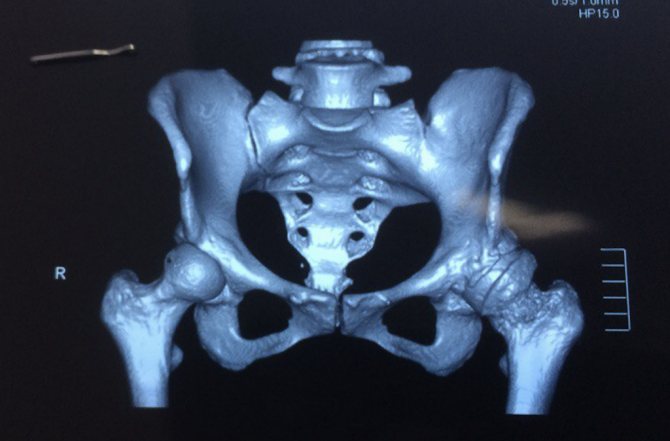

Современная инструментальная диагностика остеомиелита таза базируется на трех китах. Это радиоизотопная сцинтиграфия, магнитно-резонансная томография (МРТ) и компьютерная томография (КТ). Причем каждый из этих методов дополняет другой, а не является альтернативой. Остеосцинтиграфия наиболее информативна при остром гематогенном остеомиелите и обострении хронического. Уже с самого начала заболевания наблюдается повышенное накопление радиофармацевтического препарата (РФП) в очаге поражения, когда структурные изменения в костях еще отсутствуют. Трудно переоценить значение остеосцинтиграфии и при мультифокальном поражении скелета. Количественная оценка накопления РФП при хроническом остеомиелите позволяет объективизировать начало обострения патологического процесса.

Значимость КТ основывается на возможности детального изучения структурных изменений костей при хроническом остеомиелите: выявлении периостита, зон деструкции, секвестрации кости.